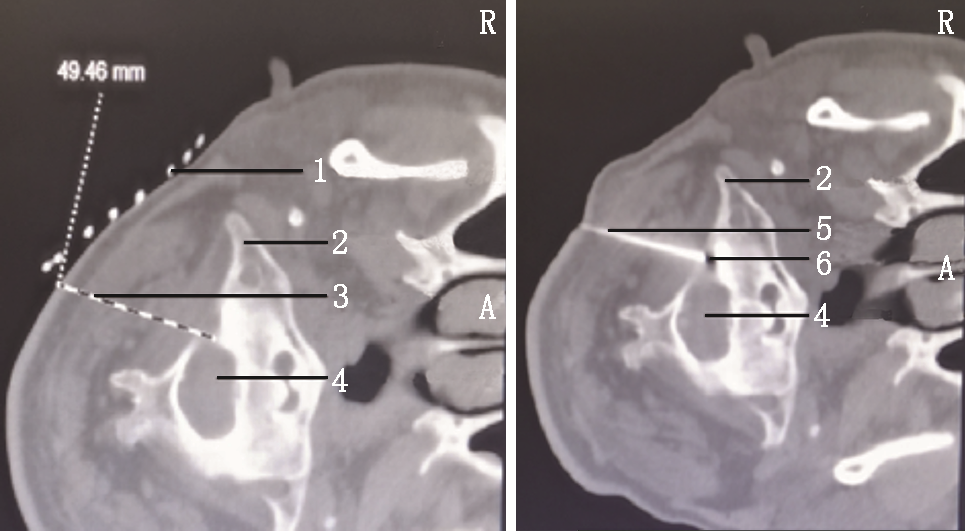

予以原方案继续口服镇痛药物,同时行眶上神经阻滞,利多卡因凝胶贴膏(北京泰德制药股份有限公司,国药准字H20180007,规格:700 mg)外贴,1贴/d,静脉抗生素抗感染、内分泌科会诊稳定血糖。入院调整3 d后,行局部麻醉下CT引导经皮穿刺半月神经节球囊压迫治疗(percutaneous microballoon compression,PMC)[3],因患者有强直性脊柱炎病史,不能平卧,予以多个体位垫辅助固定(图1),术前规划穿刺路径困难(图2)。按经典Hartel入路穿刺进入卵圆孔内口(图3A)[4],退出针芯,置入球囊导管,使远端Mark点与岩锥顶端平齐(图3B),注入30%碘海醇造影剂0.6 ml充盈球囊(图3C),球囊CT三维影像成“梨”形(图4),压迫半月节200 s,询问患者自诉右面部皮肤感觉轻度麻木,原疼痛基本消失,NRS评分2分,遂释放球囊内造影剂,拔出于球囊导管和穿刺针,结束手术。

次日查房,患诉原额头部位疼痛缓解,但同侧鼻腔出现剧烈火烧样疼痛,NRS评分7分,其所诉位置位于三叉神经第二支分布区域,故行CT引导下局部麻醉经皮穿刺圆孔三叉神经第二支射频热凝术[5],穿刺顺利,针尖在圆孔外口(图5),行95 ℃,300 s射频热凝。

第2次手术术后5 d,患者诉右侧颜面部疼痛基本缓解NRS 1~2分,但出现右侧颈枕部剧烈疼痛,是颈2神经分布区域,同时原右侧额顶部疼痛复发,爆发痛NRS评分可达6分,每天发作数十次,不能忍受,要求继续治疗。与家属说明做颈2神经根射频热凝会使同侧颈枕部出现麻木,眶上神经射频热凝会使同侧额顶部麻木,患者疼痛不能忍受,强烈要求继续行射频热凝术。因此,行经皮穿刺颈2神经根射频热凝术[6]+眶上孔眶上神经射频热凝术[7]。均采用局部麻醉CT引导模式,颈2神经根射频热凝术采用侧卧体位,术前规划穿刺路线,穿刺针到达目标靶点(图6),进行射频热凝,95 ℃、300 s,后拔出穿刺针结束,转平卧体位行眶上孔眶上神经射频热凝术,穿刺针到达眶上孔内(图7),行95 ℃、300 s射频热凝。术后颈枕部及额顶部麻木,疼痛基本消失,NRS评分1~2分,有轻微右眼不自觉流泪症状,效果满意。